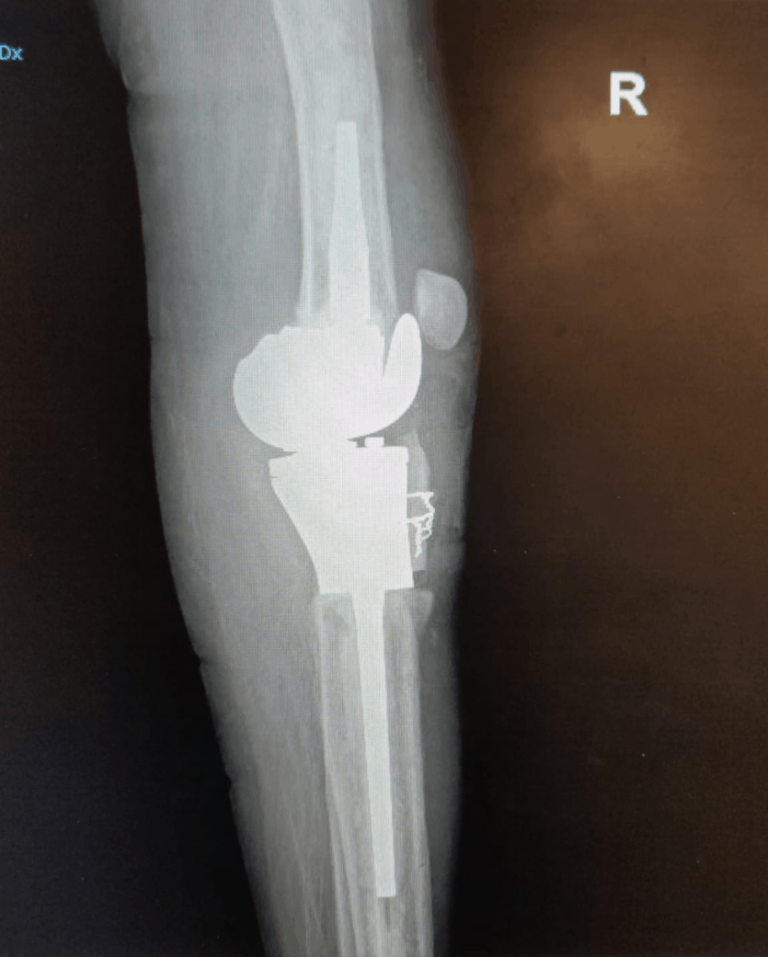

Protesi: l’intervento di revisione

Protesi: l’intervento di revisione – Quanto dura una protesi?E una delle domande […]

Protesi di ginocchio: info intervento

Protesi di ginocchio: tutto quello che si deve sapere sull’intervento.Per dare indicazione […]